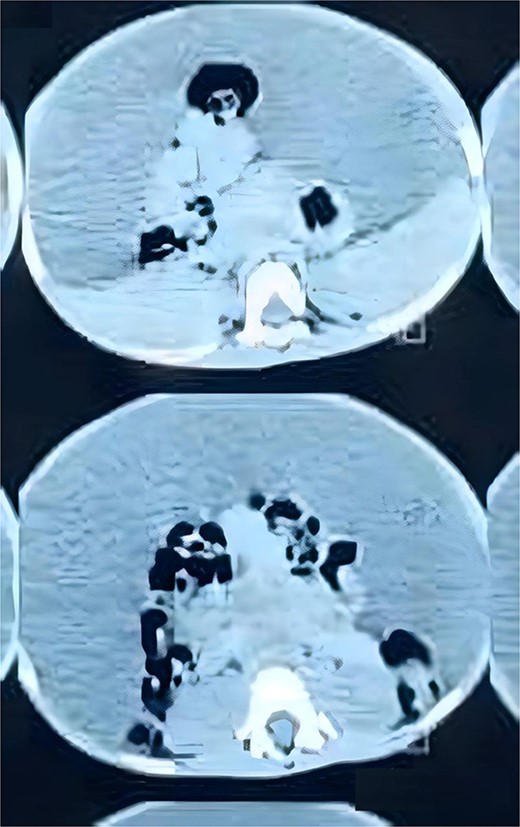

His complete blood count, serum electrolytes, renal and liver function tests were within normal range. A large cystic multiloculated abdominoscrotal lesion was highlighted in the abdominal ultrasound. The abdomen and pelvis CT with contrast showed a huge hypodense cystic lesion around 25x30 cm with hyperdense multiple internal septations without solid component causing compression and posterior displacement of bowel loops (Fig. 3). It extended through the left inguinal canal into scrotum (Fig. 4). The patient was referred to the pediatric surgery department for reassessment. Subsequently, the decision was made to go for excision.

coronal view of CT abdomen and pelvic demonstrates the scrotal extent of abdominopelvic cystic lesion